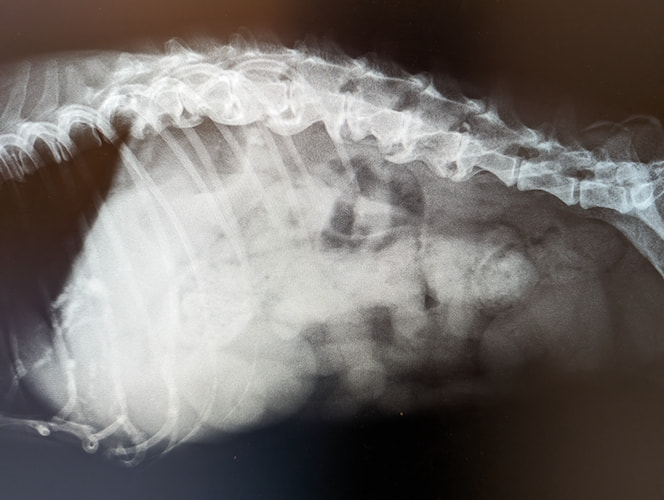

肺水腫(2025/09/01)

肺水腫は、肺に過剰な液体が貯留し、ガス交換が障害され、呼吸が苦しくなる病態です。犬猫では心原性と非心原性に大別されます。心原性肺水腫は、僧帽弁閉鎖不全症や肥大型心筋症などによる左心不全が原因で、左心房の圧が上がり、肺静脈の圧が上昇することで肺に液体が漏出して起こります。非心原性は、外傷、肺炎、敗血症、神経原性などにより血管透過性が亢進して起こります。症状は、浅くて早い呼吸、ゴロゴロとした呼吸音、咳、チアノーゼなどで、急速に悪化することがあります。胸部のレントゲンを撮影し診断を行ないます。治療は心原性では酸素吸入、利尿薬、血管拡張薬や強心薬などで行ないます。非心原性では酸素投与と原因に応じた治療を行ないます。迅速な対応が必要となる病態のため呼吸様式の異常を感じた場合は早めにご相談ください。

肥大型心筋症とは、心臓の筋肉が厚くなる病気で、猫の心臓病で最も多いとされています。筋肉が厚くなると、心臓の中の血液を貯めるスペースが狭くなり、全身に送る血液量が少なくなります。軽度の場合は無症状ですが、重度になると食欲低下、元気消失に加え、胸に水が溜まってくる(胸水貯留、肺水腫)ことがあります。また、血流が悪くなることで、血栓ができやすくなります。肥大型心筋症と診断された場合は、心臓の負担を軽減する薬を用いて進行を遅らせることが必要です。気になる症状がある場合はお気軽にご相談ください。